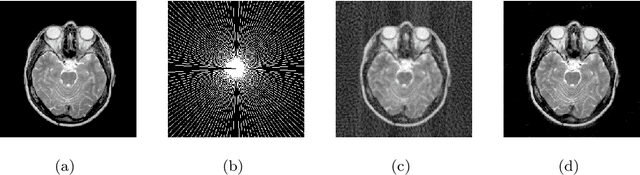

Abstract:Magnetic resonance imaging (MRI) reconstruction is an active inverse problem which can be addressed by conventional compressed sensing (CS) MRI algorithms that exploit the sparse nature of MRI in an iterative optimization-based manner. However, two main drawbacks of iterative optimization-based CSMRI methods are time-consuming and are limited in model capacity. Meanwhile, one main challenge for recent deep learning-based CSMRI is the trade-off between model performance and network size. To address the above issues, we develop a new multi-scale dilated network for MRI reconstruction with high speed and outstanding performance. Comparing to convolutional kernels with same receptive fields, dilated convolutions reduce network parameters with smaller kernels and expand receptive fields of kernels to obtain almost same information. To maintain the abundance of features, we present global and local residual learnings to extract more image edges and details. Then we utilize concatenation layers to fuse multi-scale features and residual learnings for better reconstruction. Compared with several non-deep and deep learning CSMRI algorithms, the proposed method yields better reconstruction accuracy and noticeable visual improvements. In addition, we perform the noisy setting to verify the model stability, and then extend the proposed model on a MRI super-resolution task.